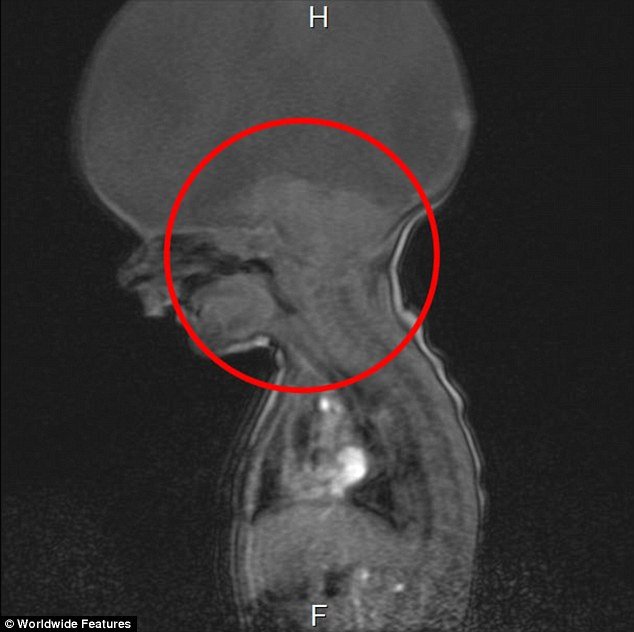

Μόλις λίγα λεπτά με τον τοκετό, το 2013, οι ιατροί είπαν ότι ο Ααρών έχει ολοπροσεγκεφαλία, μια διαταραχή κατά την οποία αποτυγχάνει η ανάπτυξη των δύο ημισφαιρίων κατά την εμβρυακή ανάπτυξη. Στην πιο σοβαρή της μορφή μπορεί να οδηγήσει σε θάνατο, ενώ σε ηπιότερη δεν επηρεάζει την εγκεφαλική λειτουργία αλλά μπορεί να οδηγήσει σε παραμορφώσεις προσώπου.

Ο μικρούλης γεννήθηκε μόνο με ένα στέλεχος του εγκεφάλου, το οποίου του επιτρέπει να αναπνέει και να κινηθεί, αλλά δεν έχει πλήρη εγκέφαλο.